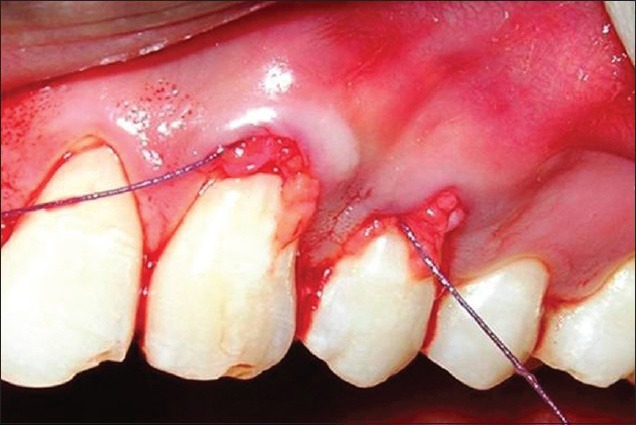

Sursă foto: PMC4296465

Tehnica de tunelizare este utilizată în tratamentul de retractii gingivale multiple adiacente pentru a permite acoperirea simultană a mai multor suprafețe radiculare, cu conservarea arhitecturii țesuturilor moi. Abordarea se bazează pe crearea unui spațiu subgingival continuu, prin incizii intrasulculare limitate, fără incizii verticale de descărcare, cu scopul de a menține integritatea papilelor interdentare și aportul vascular local.

Prin disecție atent controlată, țesuturile moi sunt mobilizate ca un ansamblu unitar, formând un tunel care se extinde dincolo de marginile fiecărei recesiuni gingivale. Acest spațiu permite inserarea unei grefe de țesut conjunctiv autogen, poziționată coronal față de joncțiunea cemento-enamel junction (CEJ), astfel încât să acopere suprafețele radiculare expuse și să fie susținută de țesuturile înconjurătoare.

Pregătirea suprafeței radiculare precede inserarea grefei și urmărește obținerea unui pat biologic favorabil adaptării tisulare. Stabilitatea inițială a complexului lambou–grefă este asigurată prin tehnici de sutură care limitează mobilitatea în perioada de vindecare timpurie, etapă esențială pentru revascularizarea și integrarea țesutului conjunctiv.

Un avantaj important al tehnicii de tunelizare este menținerea continuității țesuturilor moi, ceea ce favorizează o integrare estetică armonioasă și o vindecare predictibilă, în special în zonele frontale. Absența inciziilor verticale contribuie la păstrarea conturului gingival și la reducerea morbidității postoperatorii, aspecte constant raportate în literatura de specialitate pentru cazurile corect selecționate.